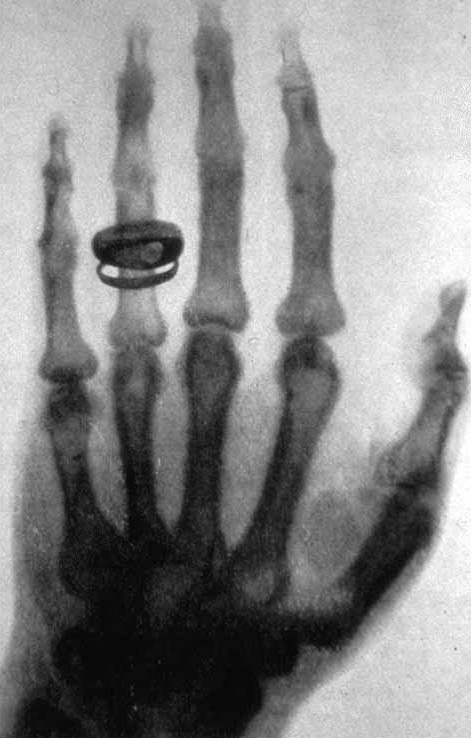

Opening X-rays. November 8, 1895.

On this day 123 years ago, a German physicist, professor and rector of a university in Bavaria, Wilhelm Konrad Roentgen, experimenting in the laboratory, unexpectedly made a discovery - the "all-pervasive" rays, which were subsequently named worldwide as X-rays.

It happened like this. After the end of the working day, Wilhelm Roentgen remained in the laboratory and experimented alone. He turned on and off the cathode tube, closed on all sides with thick black paper. Nearby were platinum cyanide barium crystals. When he turned on the tube crystals began to glow. The scientist turned off the current - the crystals ceased to glow. When the current was reapplied, the crystals resumed luminescence. As a result of further research, the scientist came to the conclusion that an unknown radiation, which he later called X-rays, comes from the tube. As it turned out, X-radiation is able to penetrate through many opaque materials. The scientist made the first pictures using X-rays.

This discovery of Wilhelm Roentgen quite strongly influenced the development of science. The study in the field of the structure of substances was completely revised and gave a new round in research in the field of classical physics.